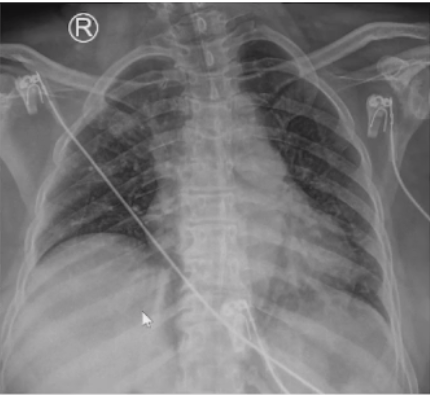

经过上述治疗,患者炎症指标有所下降(表5),胸部X线片较前好转(图7)。

8月19日复查血气分析(呼吸机辅助呼吸,SPONT模式,PSV 18 cmH2O,PEEP 8 cmH2O,氧浓度35%):pH 7.520,PaCO2 56.0 mmHg,PaO2 144.0 mmHg,SaO2 99%。SBT通过,复查支气管镜见气道内少许分泌物,黏膜光滑无肿胀,于8月19日脱机拔管,序贯无创呼吸机辅助呼吸。气管导管尖端培养、灌洗液培养(8月19日送检)均为肺炎克雷伯杆菌;血培养(8月16日送检)为白色念珠菌。血NGS回报金黄色葡萄球菌(序列数3),覆盖度0.01%。继续延用替加环素+多黏菌素B+卡泊芬净的治疗方案。患者8月19日拔管后仍出现反复发热,考虑仍与感染有关。然而,从8月21日胸部X线片可见肺部病变有所好转(图8)。8月22日胸部CT可见两侧胸腔积液明显吸收,双肺实变、渗出灶较前明显好转(图9)。考虑患者发热的原因可能并非肺部感染。8月23日查体见患者背部、腹股沟区、左下肢点片状红疹。考虑可能为药物热所致,遂停用多黏菌素B、替加环素,改为哌拉西林他唑巴坦4.5 g ivgtt q8h抗感染治疗,继续卡泊芬净抗真菌治疗。调整治疗方案后患者最高体温下降,但仍有发热。为了排查感染问题,8月26日拔除PICC管,之后2~3天,患者体温逐渐恢复正常。因此考虑患者可能合并血流感染。之后患者一般情况好转,8月27日复查胸部X线片提示病情进一步好转(图10)。8月29日转入普通病房,后一直未再发热,9月13日出院。